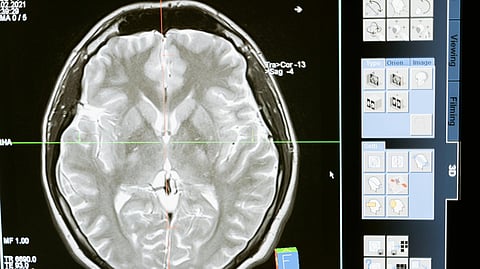

A brian scan

An MRI scan revealed a lesion in the frontal lobe of her brain, prompting urgent neurosurgical evaluation. MART PRODUCTION/Pexels

An MRI scan revealed a lesion in the frontal lobe of her brain, prompting urgent neurosurgical evaluation. This marked a turning point, as doctors suspected the disease had spread beyond the lungs and internal organs.